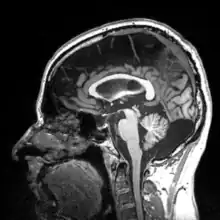

More recently, computed tomography has played a large role in reconstructing endocasts. The procedure is non-invasive and has the advantage of being able to analyze a fossil in record time with little risk of damaging the fossil under review. CT imaging is achieved through the application of x-rays to produce tomographs, or sectional density images, which are similar to the images produced during MRI scans.[8] CT scans use slices approximately 1 mm thick to reconstruct a virtual model of the specimen.[9] This method is especially useful when a fossil cranium is occupied by a natural endocast that cannot be removed without destroying the skeletal portions of the fossil. Because the cranium and its contents are of different densities, the endocranial cavity and its unique traits can be reconstructed virtually.[8]